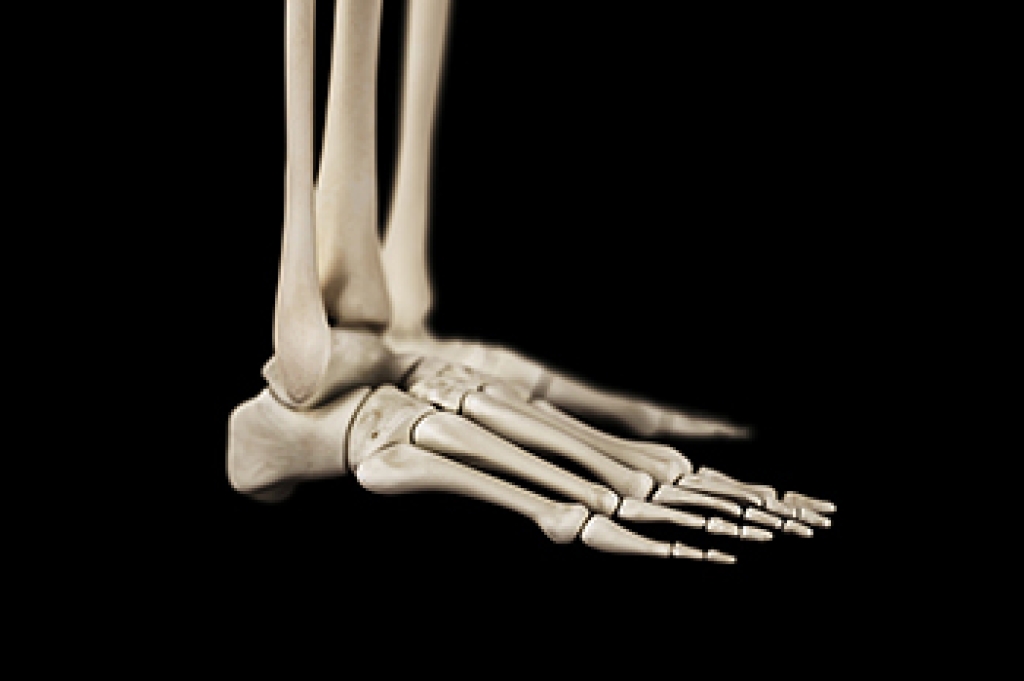

Heel spurs are formed by calcium deposits on the back of the foot where the heel is. This can also be caused by small fragments of bone breaking off one section of the foot, attaching onto the back of the foot. Heel spurs can also be bone growth on the back of the foot and may grow in the direction of the arch of the foot.